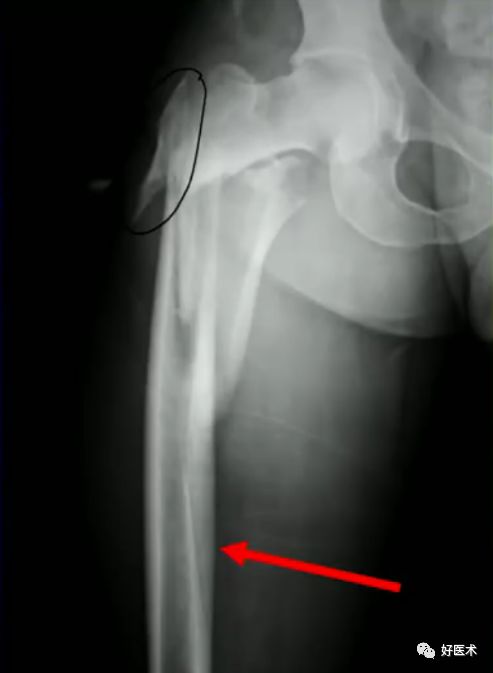

5.避免进钉点失误

进钉点偏外易造成髋内翻

头钉的尾部要置于外侧骨皮质外而不能埋入皮质下

6.正确的股骨颈正侧位

侧卧位如何透股骨颈的侧位:

-

标准侧位

球管20-30°